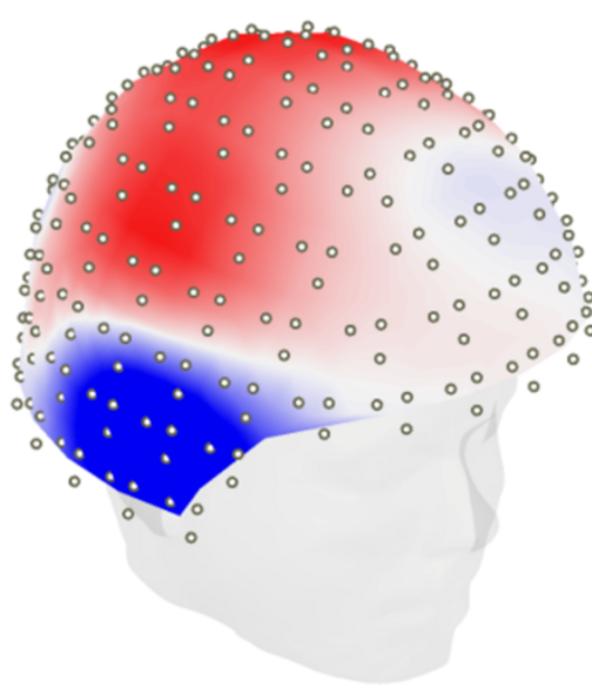

The team led by Jonathan Gallego Rudolf, a Ph.D. candidate in Baillet and Villeneuve’s labs, recruited 104 people with a family history of Alzheimer’s. They scanned the participants’ brains using a combination of positron emission tomography (PET) to detect the presence and location of the proteins and magnetoencephalography (MEG) to record brain activity in these regions.

The scientists compared the results of the two scans and found that brain areas with increased levels of amyloid-beta showed macroscopic expressions of brain hyperactivity, reflected by increased fast- and decreased slow-frequency brain activity. For people with both amyloid-beta and tau in their brain, the pattern shifted towards hypoactivity, with higher levels of pathology leading to brain activity slowing.

Using cognitive tests, the team discovered that participants with higher rates of this amyloid-tau related brain slowing showed higher levels of decline in attention and memory.